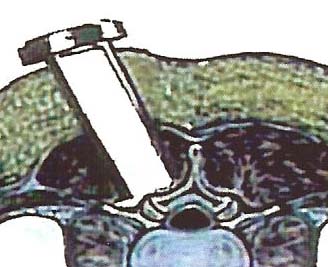

Our areas of practice include Spinal

Surgery and Pain

Procedures